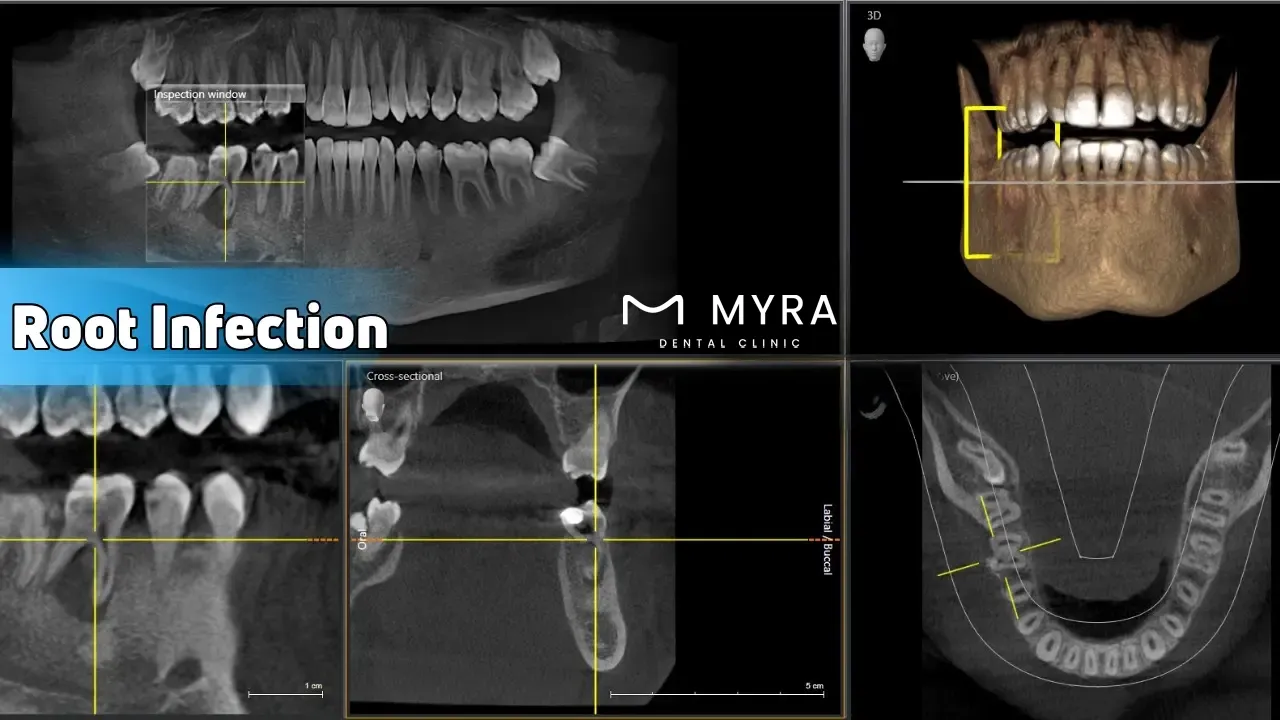

Root infection is a severe condition affecting the tooth's most sensitive area. Root infection occurs when bacteria invade the tooth's pulp, leading to infection and inflammation. It causes pain and discomfort, leading to serious dental issues if left untreated. Understanding the symptoms, treatment options, causes, and similar situations helps manage and prevent root infections effectively.

Treating a root infection involves several steps to eliminate the infection and preserve the tooth. The most common treatment is a root canal, where the infected pulp is removed, and the inside of the tooth is cleaned, disinfected, and sealed. A tooth extraction is necessary to prevent the spread of infection. Draining any abscesses that have formed part of the treatment process. Antibiotics are prescribed to control and eliminate the disease, mainly if it has spread beyond the tooth.

Root infections are caused by bacteria entering the tooth's pulp through various means. A common cause is tooth decay, where cavities penetrate deep into the tooth. Cracks or chips in the tooth provide an entry point for bacteria. Damage to the tooth pulp, whether due to trauma or repeated dental procedures, increases the risk of infection. A fractured tooth root exposes the pulp and leads to infection.